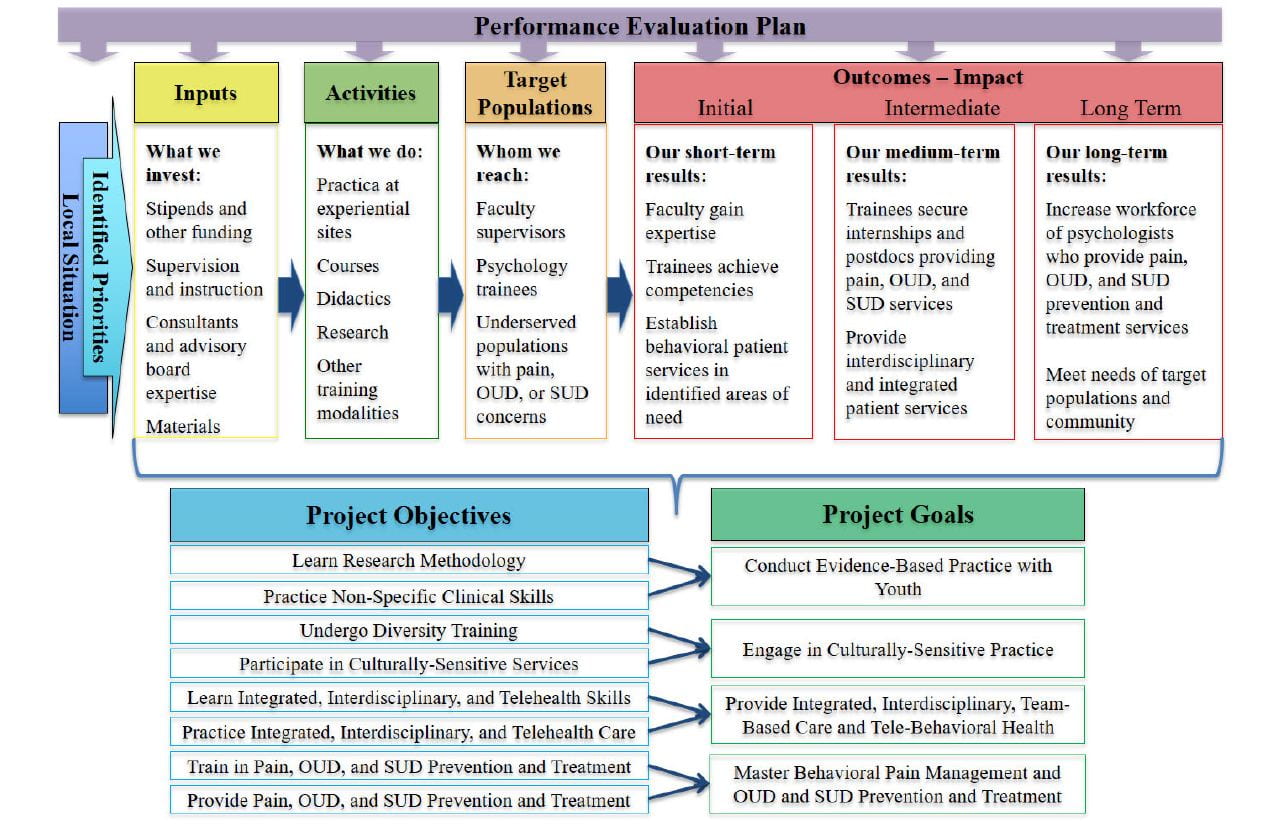

TIPPS aims are to train psychology students to 1) conduct evidence-based practice with youth; 2) engage in culturally-sensitive practice; 3) provide integrated, interdisciplinary, team-based care and tele-behavioral health; and 4) master behavioral pain management and opioid use disorder and substance use disorder prevention and treatment.